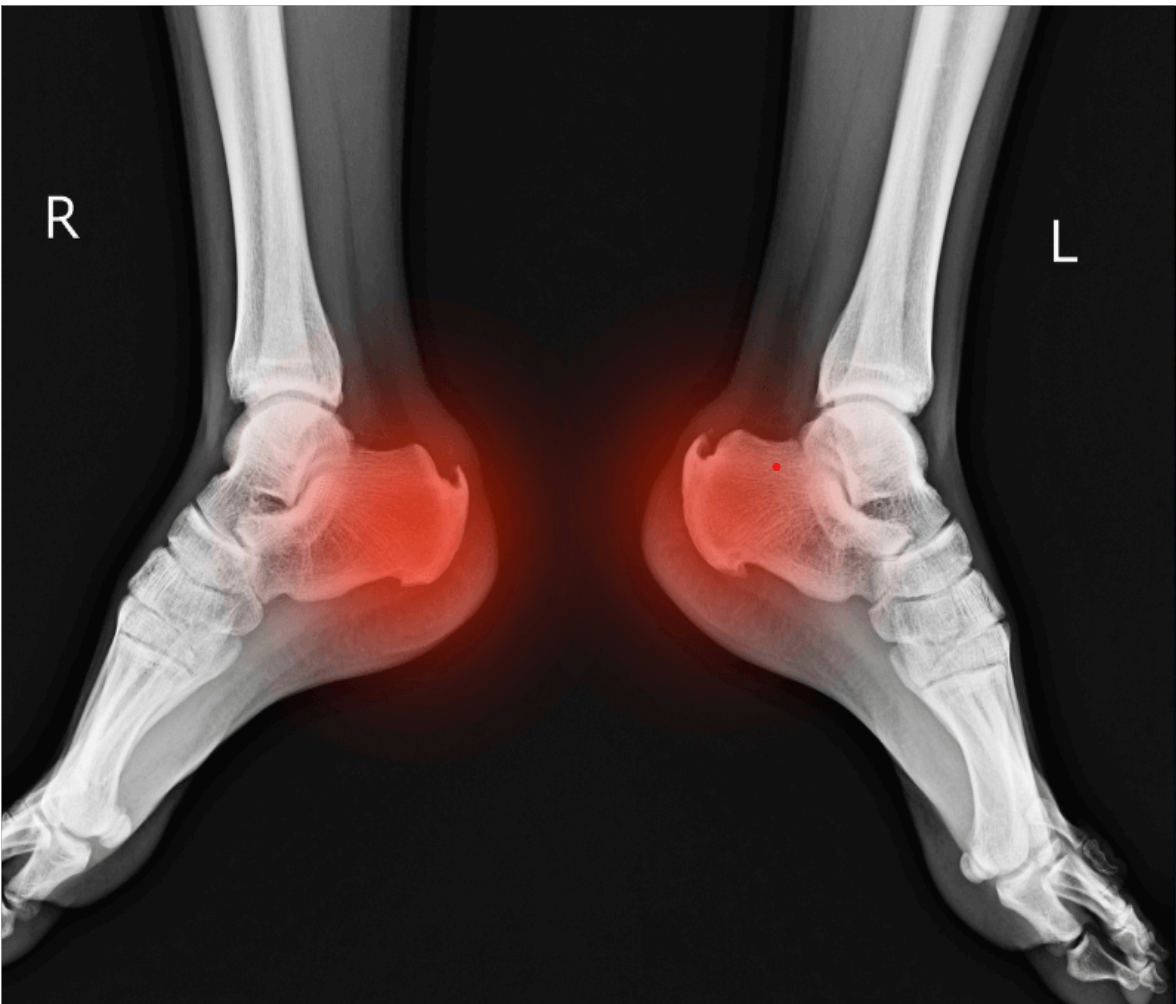

Phục hồi chức năng bệnh lý cơ xương khớp

Tôi bị đau gót chân đã lâu. Đã điều trị bằng phương pháp châm cứu bấm huyệt, được người quen giới thiệu cô đến trung tâm và được cháu Viện, kỹ thuật viên tại trung tâm kiểm tra tình trạng, đưa ra hướng điều trị. Sau 10 buổi bắn xung kích cô đã đỡ đau được 80% , ngoài ra bên trung tâm luôn kiểm tra lịch nhắc hẹn để cô đi điều trị đúng liệu trình để không ảnh hưởng tiến độ trị liệu

Cô Ngọc Anh - Nghỉ hưu

Giảm đau đến 80% chỉ sau 10 buổi điều trị